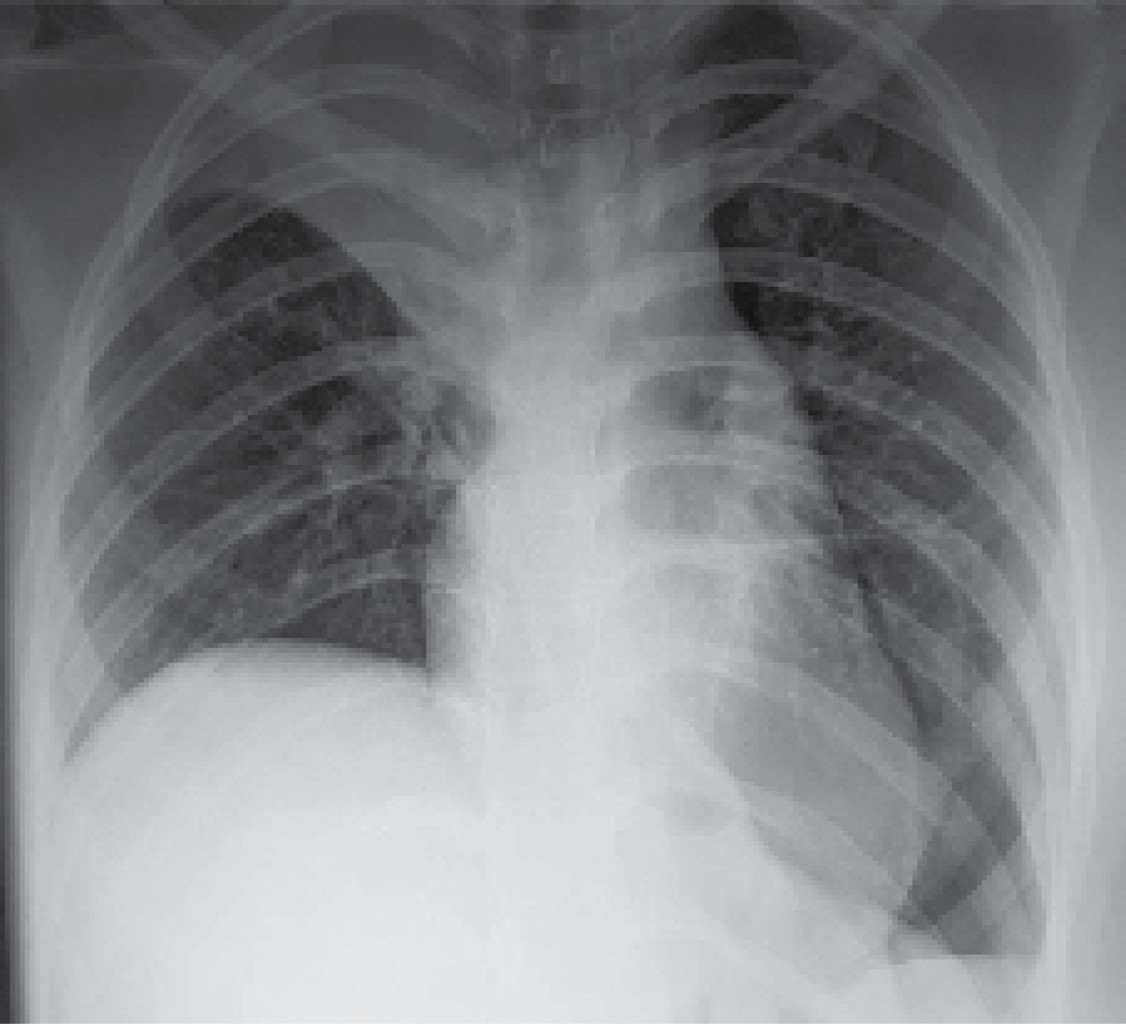

Se solicita radiografía de tórax de control, con evidencia de atelectasia apical derecha, con neumotórax basal mínimo izquierdo, por lo cual se egresa a la paciente para manejo por consulta externa a las 48 horas de su postoperatorio (Figura 4).

Figura 4